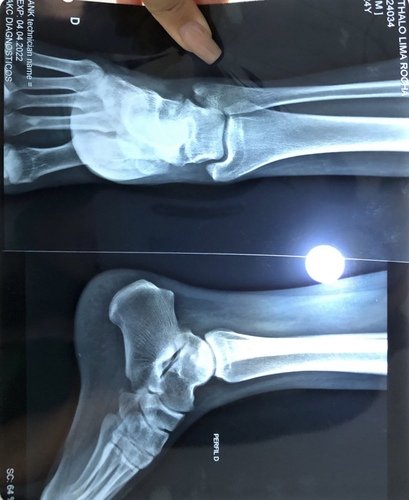

Me chamo Ythalo, tenho 25 anos, há quase um ano no dia 26/02/2022 sofri uma fratura no tornozelo do pé direito, no início pensei que não fosse nada grave, mas ao consultar me informaram que tinha um pequeno derrame articular e houve uma fratura lateral do corpo do tálus. Tive um repouso de 60 dias, e houve um pouco de alívio da dor, voltei as atividades normais, mas ao passar do tempo a dor voltou e foi aumentando cada vez mais. Fiz uma nova consulta e o médico me informou que devo fazer a cirurgia. Hoje me encontro sem trabalhar a 02 meses por não conseguir por causa da dor, e na fila do sus para a cirurgia a 05 meses, mas pelo fato de ainda não terem me chamado para a cirurgia decidi criar a Vakinha para fazer ela o mais rápido no particular, a cirurgia custa 6.000,00 e vou ter que fazer uma nova tomografia e uma nova consulta que vão ficar no valor de 1.000,00. Preciso voltar a trabalhar e voltar as minhas atividades normais, mas isso só será possível após essa cirurgia. Conto com sua ajuda e serei muito grato.